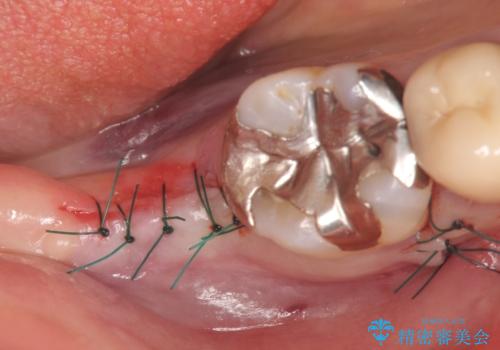

CT撮影を行い状態を確認後、インプラント(ストローマン)の埋入(一次手術)を行いました。

インプラントと骨の定着を待った後に二次手術を行い、カスタムアバットメント、オールセラミッククラウンによる補綴を行いました。

- 外科手術のため、術後に痛みや腫れ、違和感を伴います